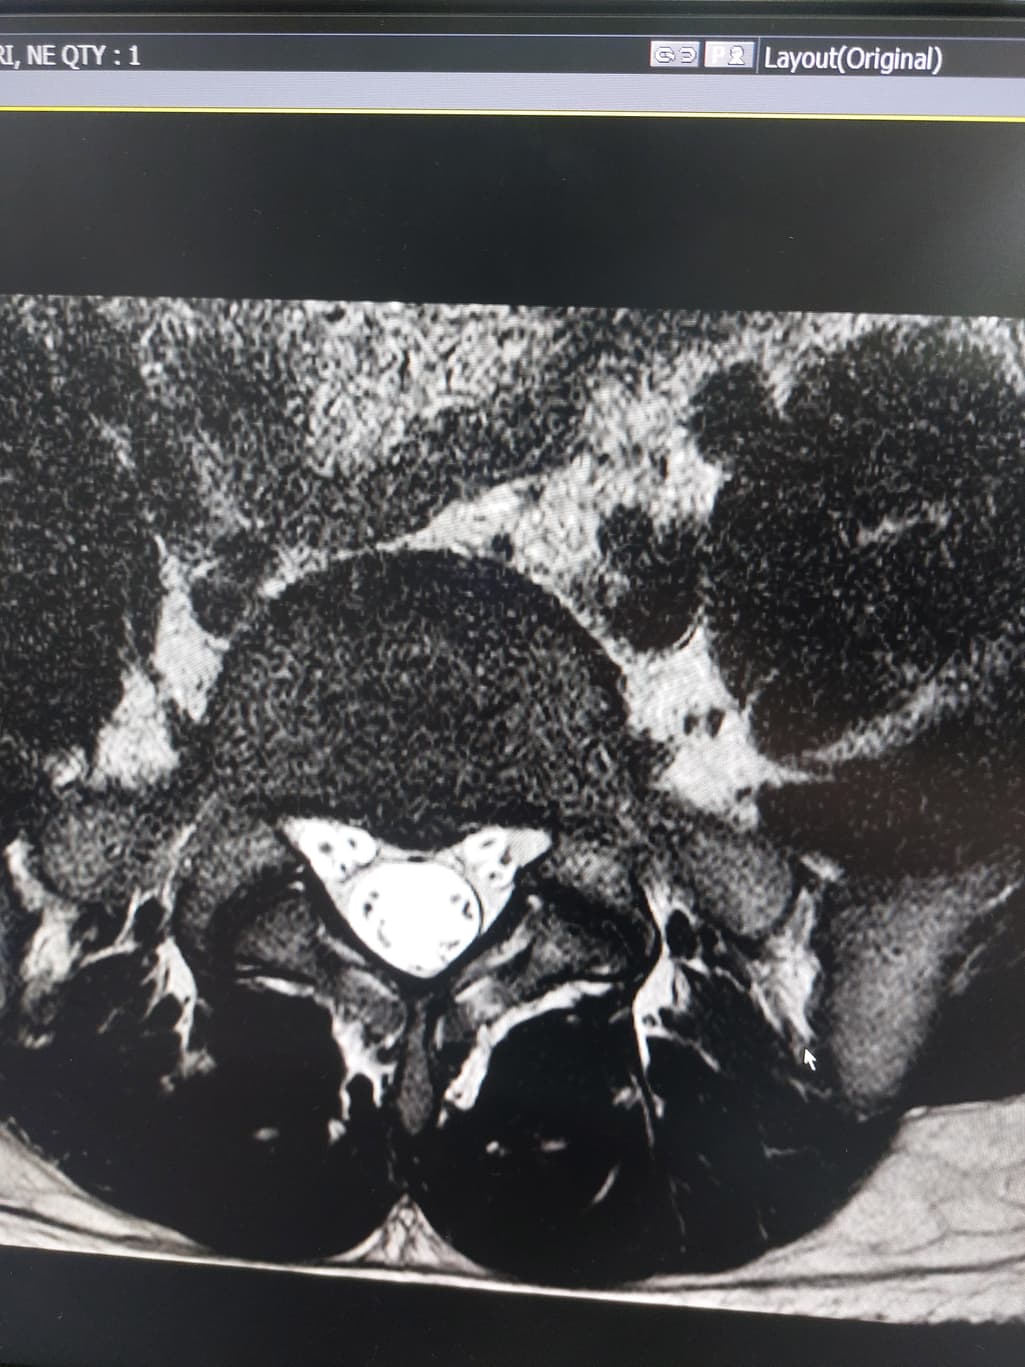

허리디스크 심한편인가요? [Mri 사진 첨부]

멸개월전부터 요추가 뻣뻣하고 시큰거리다가 최근에 좀 나아지긴 해도 만성적이라서 오늘 mri 찍고 허리디스크 진단받았습니다

(요추 맨 밑 천추 위 디스크)

신경이 심하게 눌리고 있지는 않은 것으로 보입니다. 충분히 휴식하여 주시고, 허리에 무리가 많이가는 자세는 당분간은 피해주시는 것이 좋습니다.